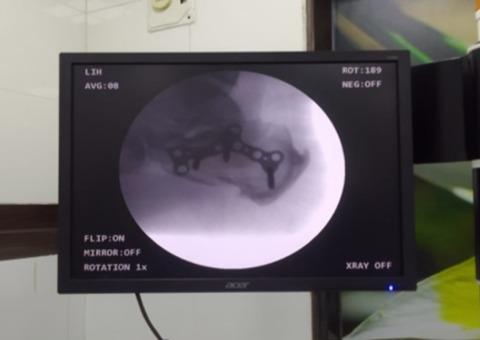

July’24 – Ortho surgery for 4 to 5 hours to join bones with a plate was done successfully for the first time in Kola hospital